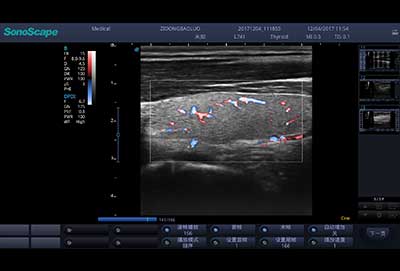

血管内中膜自动测量

E3便携式彩色多普勒超声诊断系统拥有专业超声技术平台、高度集成化的硬件模块和结构设计、简便的操作流程、支持三探头接口全激活,兼顾了优质图像、轻便机身以及台便两用的临床使用需求。无论在常规超声科门诊检查,还是在急诊、麻醉、ICU、户外等各种应用场景。都能给您带来流程的操作体验。